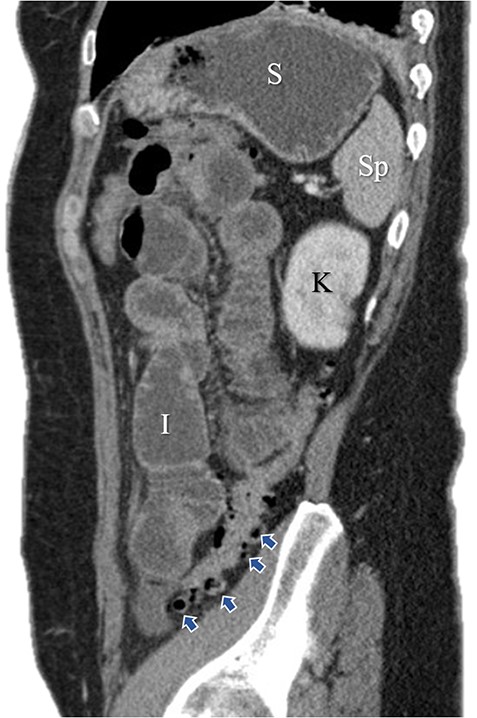

Immediate postoperative course was uneventful until postoperative day (POD)-5 when she experienced multiple watery stools, diffuse abdominal pain, fever (102.6F) and leukocytosis (23000/UL). Clostridium difficile infection was ruled out with a negative stool toxin assay. Her abdominal exam remained nonspecific until POD-6 when she had bilious emesis. A computed tomography (CT) scan revealed perforated diverticulitis with pelvic abscess and multiple colonic diverticulitis with an associated small bowel obstruction (SBO) (Images 1–4). No prior history of diverticulitis was reported.

Sagittal image of colonic diverticuli. S: stomach; Sp: spleen; K: kidney; I: ileum; Blue arrows: multiple colonic diverticuli.